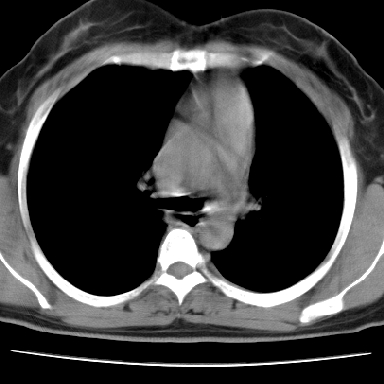

f 37 咳嗽1周,咯血1次,无浓痰,无明显发热

左下肺肿块影,内可以见小泡征,并见厚壁空洞形成,洞内缘凹凸不平,可见壁结节。靠近胸膜侧可见胸膜凹陷征。左侧胸腔内可见少量低密度积液影。右肺可见两处高致密的小结节影。

考虑:左下肺周围型肺癌伴右肺转移

左下肺肿块影,内可以见小泡征,并见厚壁空洞形成,洞内缘凹凸不平,可见壁结节。靠近胸膜侧可见胸膜凹陷征。左侧胸腔内可见少量低密度积液影。双肺可见多发性小结节影。

考虑:左下肺癌性空洞伴两肺转移